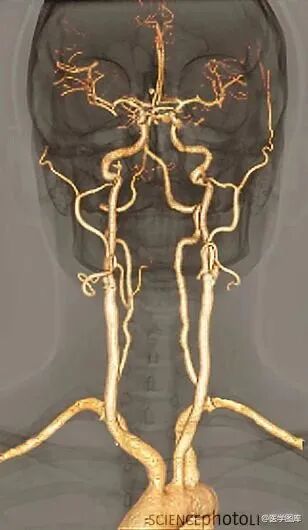

3.大脑供血动脉3D扫描CT成像